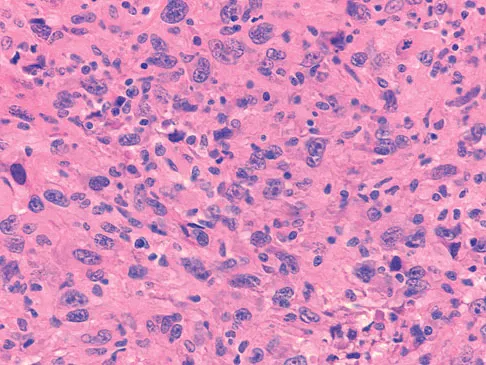

Figures 1a through 1c show the radiograph and MRI scans of a 16-year-old patient who has a painful hip. Examination reveals a significant limp, limited abduction and internal rotation, and severe pain with internal rotation and adduction. A biopsy specimen is shown in Figure 1d. What is the deposited pigment observed in this condition?

Pigmented villonodular synovitis (PVNS) is a synovial proliferative disorder that remains a diagnostic difficulty. The most common clinical features are mechanical pain and limited joint motion. On radiographs, the classic finding is often a large lesion, associated with multiple lucencies. Other findings may include a normal radiographic appearance, loss of joint space, osteonecrosis of the femoral head, or acetabular protrusion. MRI is the imaging modality of choice and will show the characteristic findings of a joint effusion, synovial proliferation, and bulging of the hip. The synovial lining has a low signal on T1- and T2-weighted images, secondary to hemosiderin deposition. Copper deposition occurs in patients with Wilson's disease, which mainly affects the liver. Bhimani MA, Wenz JF, Frassica FJ: Pigmented villonodular synovitis: Keys to early diagnosis. Clin Orthop 2001;386:197-202.